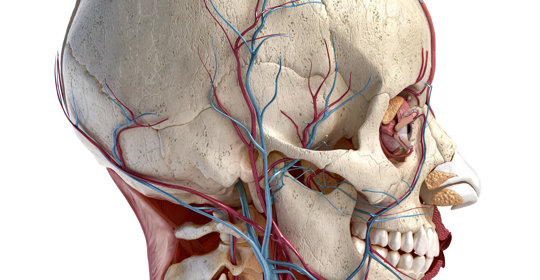

脊柱相關疾病診斷與症狀、劇烈神經根性痛

幻肢痛治療:五大修復神經系統食物